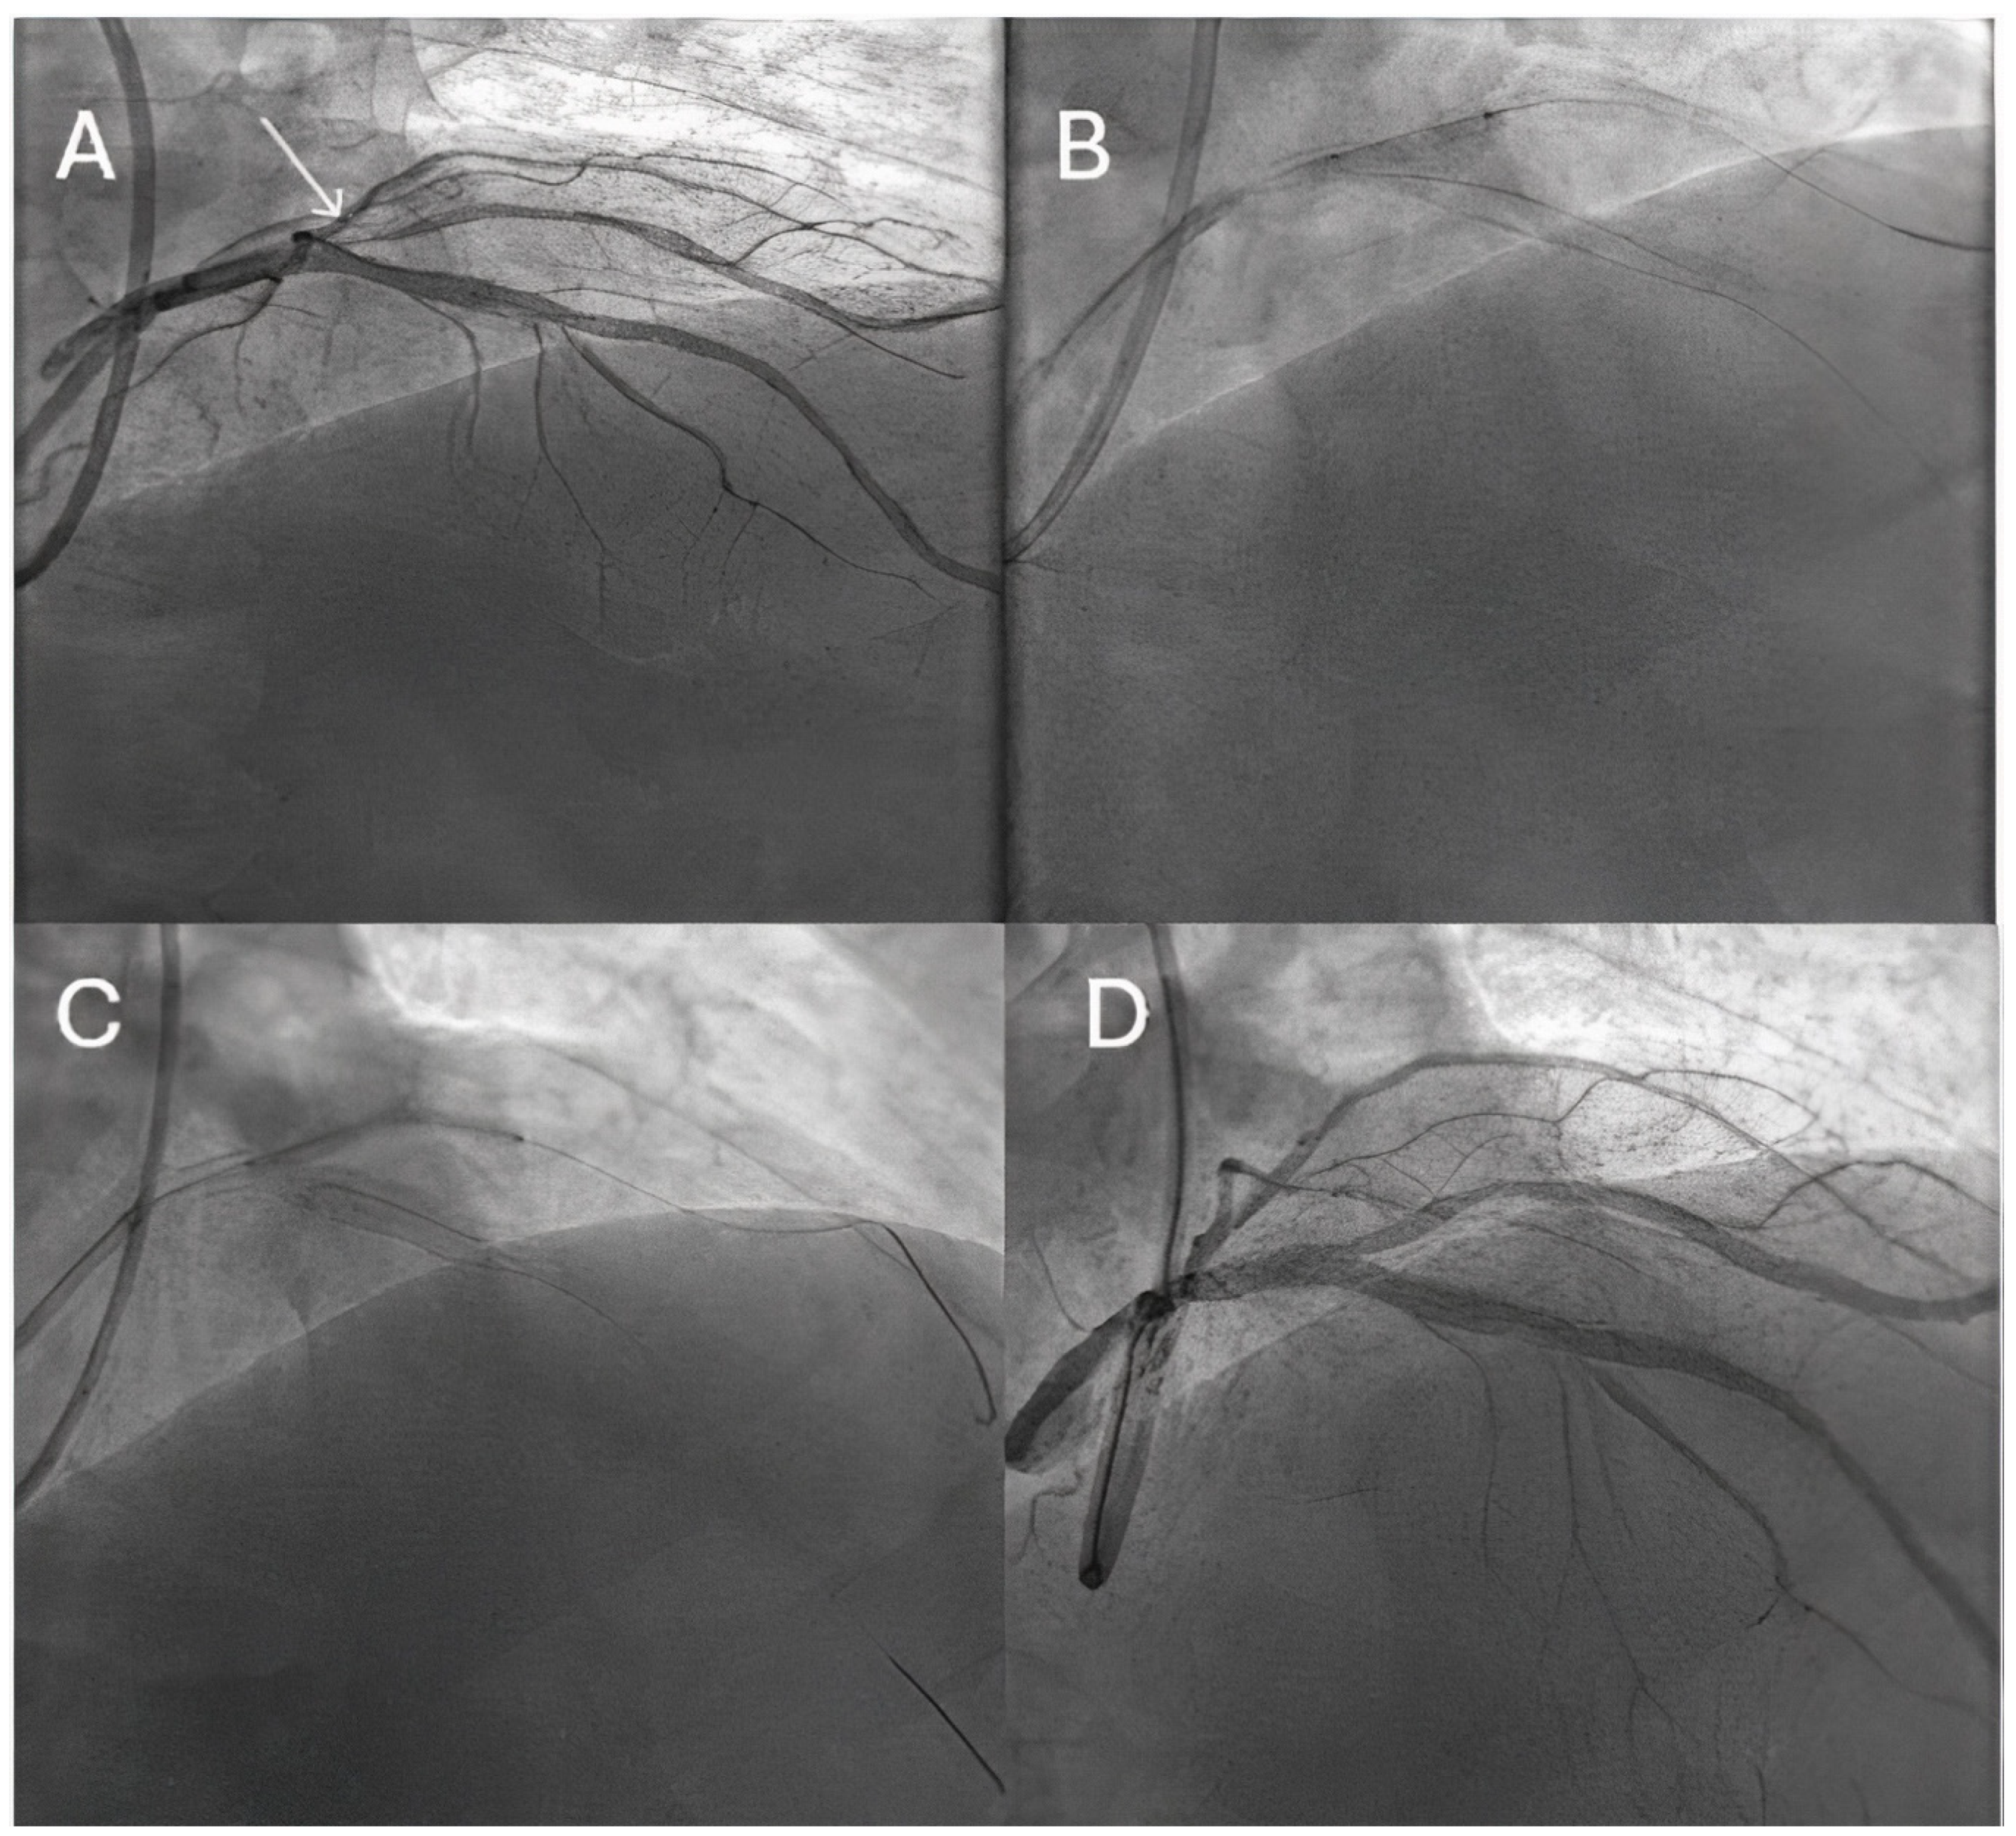

- Uskela, S.; Eranti, A.; Kärkkäinen, J.M.; Rissanen, T.T. Drug-coated balloon-only strategy for percutaneous coronary intervention of de novo left main coronary artery disease: The importance of proper lesion preparation. Front. Med. 2023, 17, 75–84. [Google Scholar] [CrossRef]